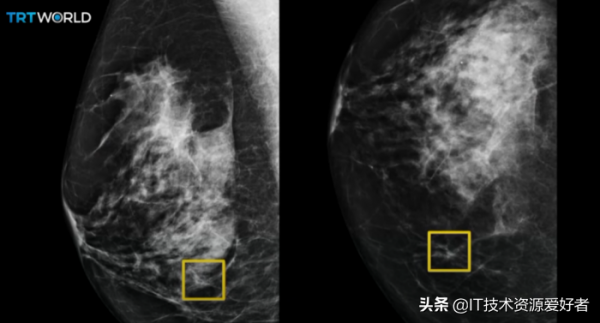

谷歌健康的 AI 能比專家更準確的檢查出乳房癌症。

英國每一年都有超過 55000 人被診斷出乳腺癌,而美國那邊每 8 名婦女就會有 1 人在有生之年患上乳腺癌。

關鍵是多數的乳腺癌症狀在前期表現都不明顯,很容易被忽視或者沒有及時被篩查出來。

而谷歌去年一月發表在《 Nature 》的一篇文章,分享了 AI 是如何準確識別女性乳腺癌的早期跡象。

谷歌聯合 DeepMind 、英國癌症研究中心、西北大學,採集了來自英國 76000 多名、美國 15000 多名女性的 X 光檢查資料。

基於這些資料訓練出來的 AI 模型,檢查了英國 25000 多名和美國 3000 多名的 X 光檢查樣片。

相較於人工篩查, AI 在美國減少了 5.7% 的乳腺癌誤報,在英國減少了 1.2% 。

僅透過觀察 X 射線實片來對乳腺癌進行篩查,這個 AI 模型在識別乳腺癌的準確率方面早就超過了部分專家。